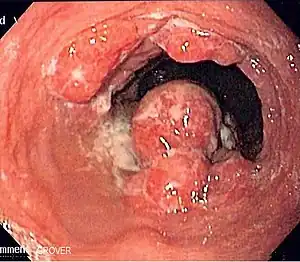

| Endoscopic image of an esophageal adenocarcinoma | |